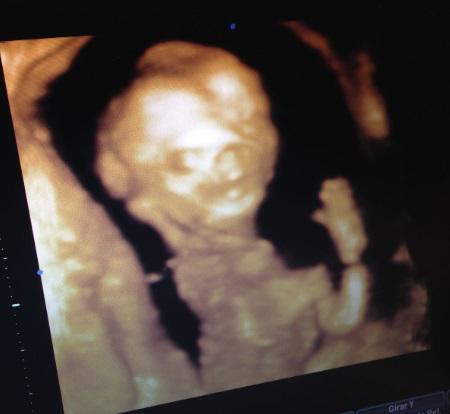

Que chicas más atentas y más agradables, nos explicaron cada posición del bebé, iban intercambiando imagenes en 3d con imágenes en 4d alternativamente explicándonos cada parte. No paraba de moverse…en otras ocasiones ya os he comentado que parece que viene algo inquieto y aquí volvía a moverse y “hacía el pino”. Se centraron especialmente en la parte del culete a ver si nos dejaba ver sus encantos y ahí estaba saludándonos.

ppp

Había otra chica que hacía las ecografías y se intercambió con la que estaba sin decirse el sexo la una a la otra y ver si coincidian y si, las dos nos dijeron lo mismo.

Es una nena